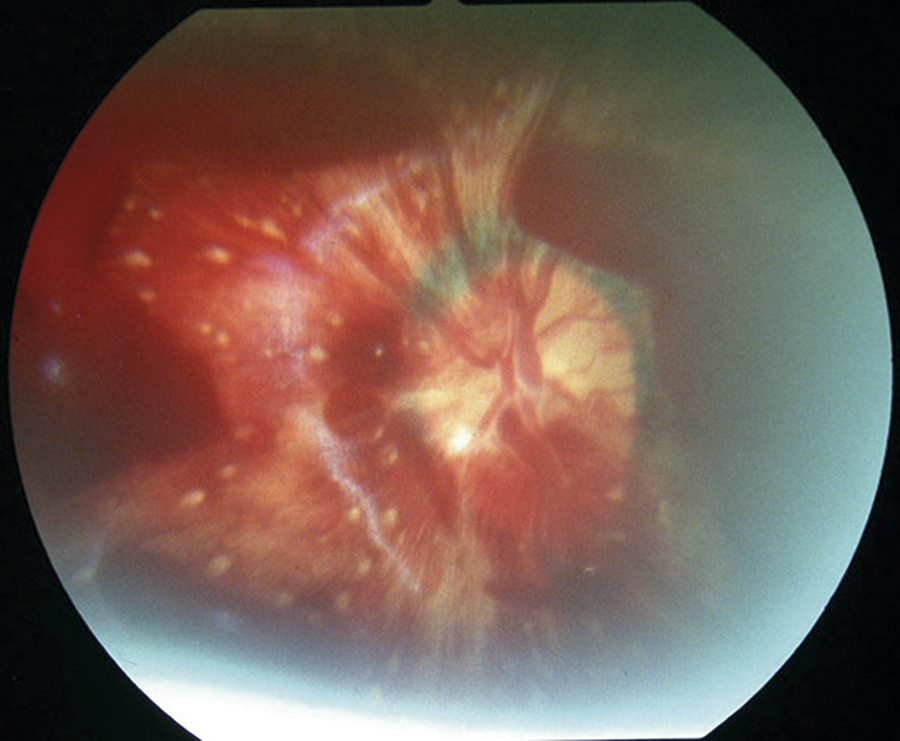

Figur 2. Retinoschis, dvs upplyftad näthinna, hos barn som utsatts för AHT. Runt schisblåsan finns depigmenterade ljusa veck i näthinnan. Intraretinala punktblödningar, som är för många att räkna. Preretinala blödningar.